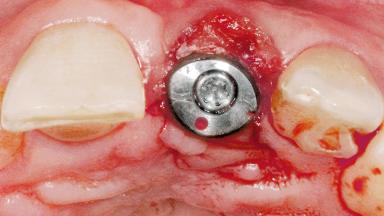

Late Flapless Placement of an Implant in a Maxillary Left Central Incisor Site

A 39-year-old male patient presented with a chief complaint of discomfort and gingival discoloration around his maxillary left central incisor. He was in good general health and was a non-smoker. His past dental history was significant because of the traumatic fracture of tooth 21 in a sporting accident at age 13. Initial dental treatment included endodontic therapy and a full-coverage restoration. The patient became symptomatic 5 years later, when structural failure of the tooth resulted in the dislodgment of the crown. Endodontic retreatment, apical surgery, and post-and-core restoration were performed.

Type of Implants One-Piece

Attachment One-Piece

Bone Volume Deficient horizontally, requiring prior grafting